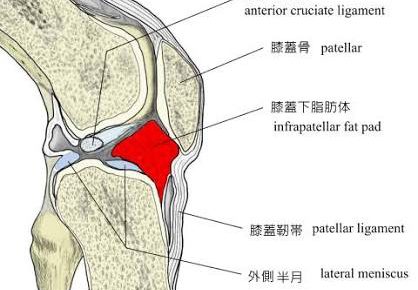

おはようございます!横浜本牧パーソナルトレーナー宮原崇です。 昨夜の上半身のトレーニングが早速心地よい筋肉痛に変わり、朝からやる気になります。もう一つやる気の原因は大変お世話になっている社長さんがテレビ出演されていて、世…

こんにちは!横浜本牧パーソナルトレーナー宮原崇です。 成人式で話題になった、横浜中区の会社が謝罪会見を行ったというニュースが今朝の新聞の一面となっておりました。色々な意見があるとは思いますが、やはり何事においても人間性と…

こんばんは!横浜本牧パーソナルトレーナー宮原崇です。 朝から吉田松陰の本を読んで、日本人の気質について考えておりました。猛スピードで時代の変化が起きていますが、人間として大切な原理原則はそう変わらないのではないかと思いま…